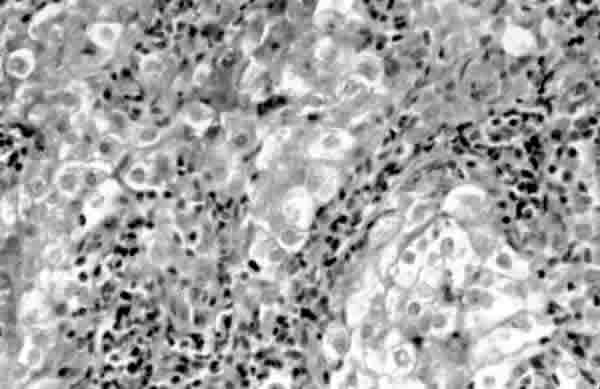

Fig. 9. Histopatología glassy cell carcinoma.